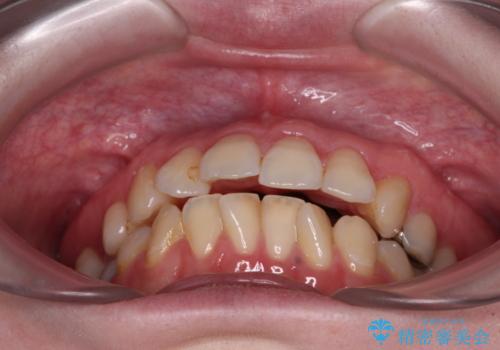

開咬と前方に飛び出した前歯 インビザラインによる矯正治療

- 上下前歯の非接触と叢生を気にして来院された患者様です。

開咬の改善はインビザラインの最も得意とするところであるため、インビザラインを用いて矯正治療を行うこととしました。

舌の突出癖改善のトレーニングをしっかりと行っていただき、上下前歯が接触する咬み合わせを達成することができました。